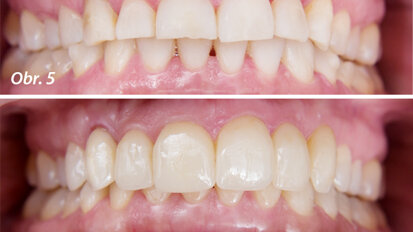

Hybridní terapie alignery